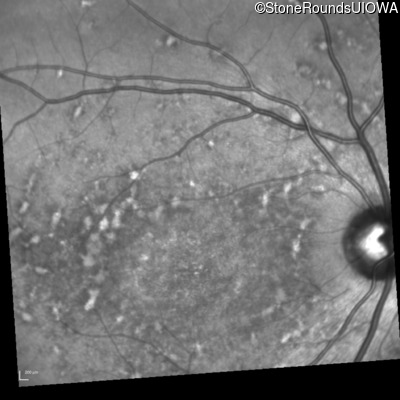

Age at visit: 22 years

OD OS

Age at visit: 17 years

Age at visit: 18 years

Age at visit: 19 years